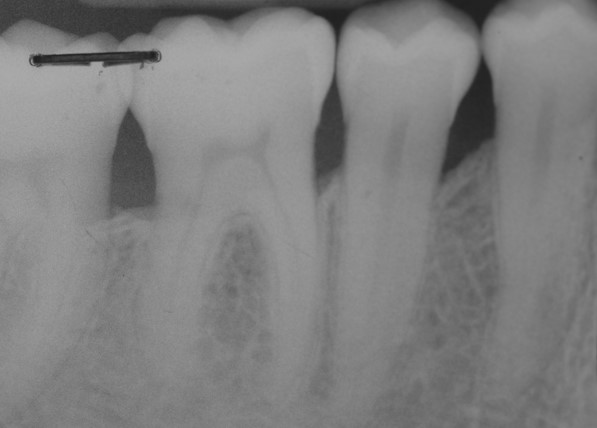

17/22 - Radiographic follow up 12 months post-operative. The radiograph demonstrates a complete defect fill and a stable result.

Deep intrabony defects treated using Straumann® Emdogain® - Dr. M. Stefanini